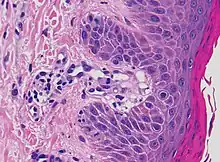

| Kaposi’s sarcoma in patch stage | The patch stage typically shows irregular proliferation of jagged vascular channels in the dermis below an integral epidermis. The so-called promontory sign is sometimes found in patch stage lesions and denotes vascular spaces surrounding pre-existing blood (see image).[23]

vessels |

![]() |